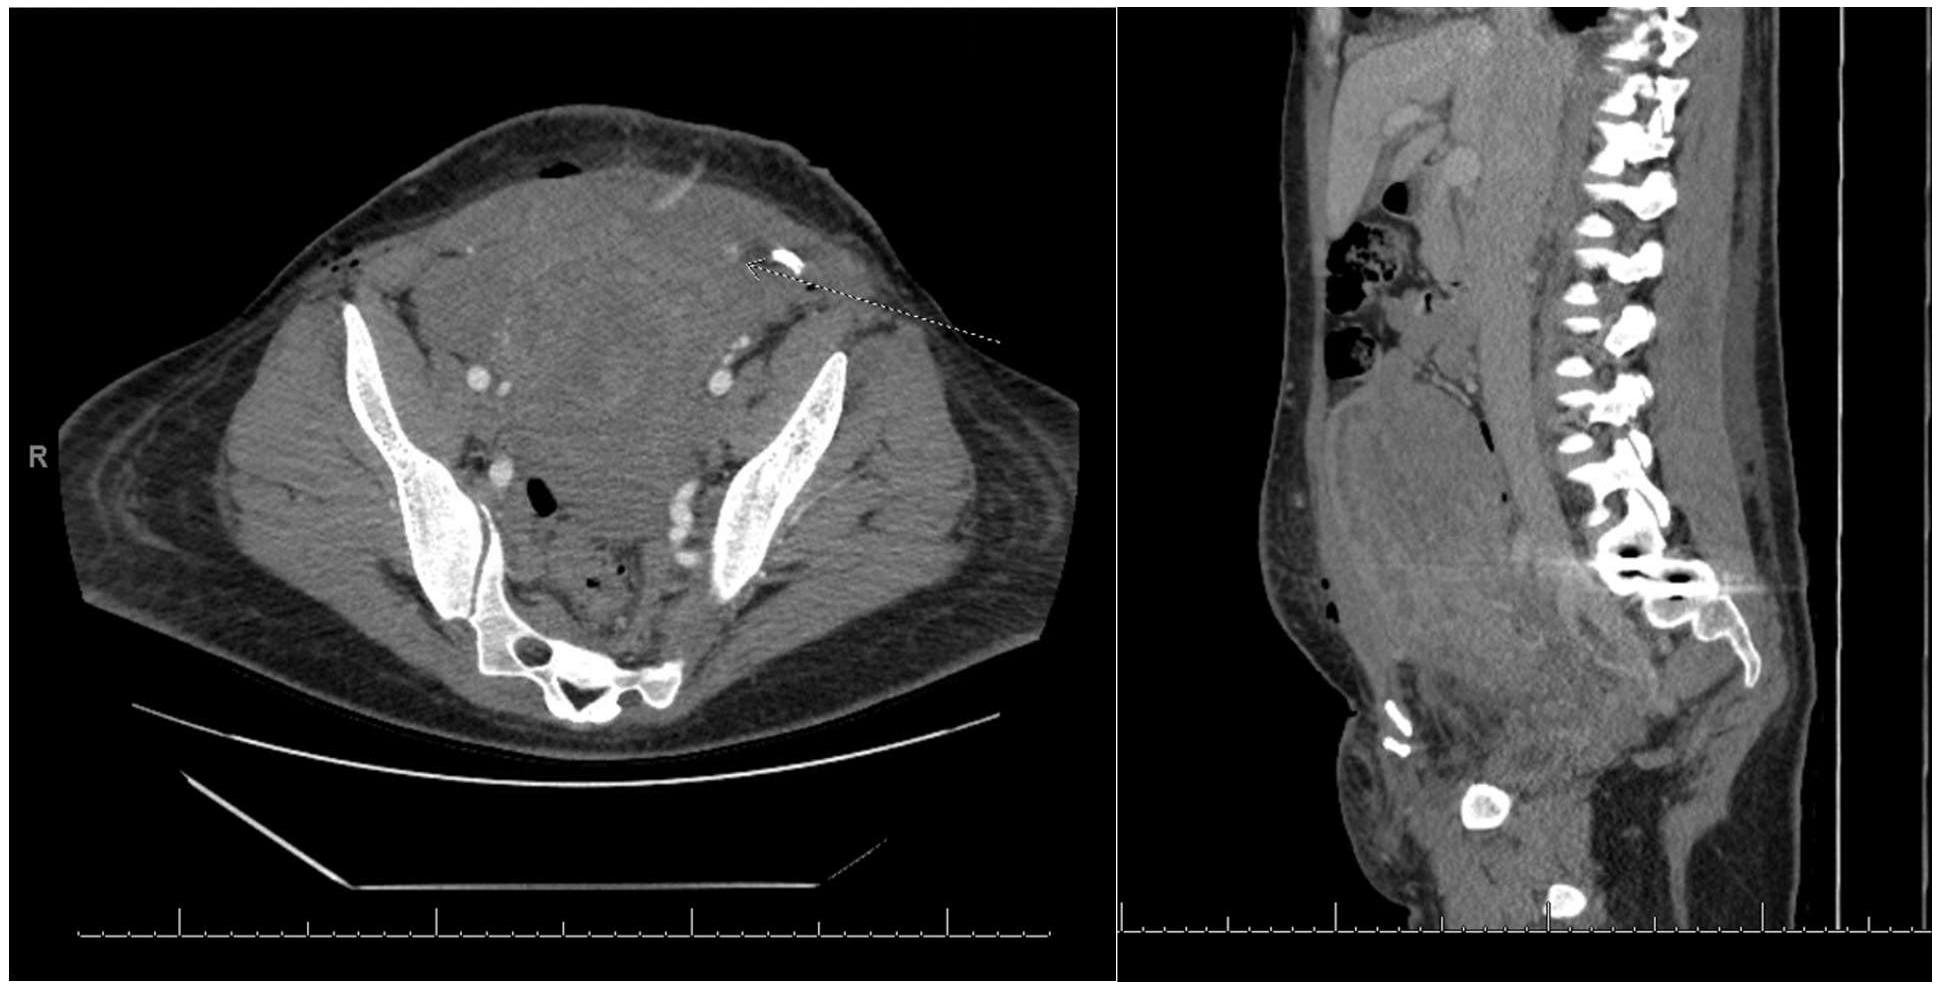

While being evaluated in the recovery unit, the JP drain had an output of 200 cc of bright red blood. At that time her hemoglobin was 6.3 g/dL with a fibrinogen of 186 mg/dL (PT 15.1 seconds and INR 1.2). A CT scan of the abdomen/pelvis (Figure 3) revealed a small collection of blood within the rectus sheath in addition to hemoperitoneum anterior to the uterus. An “abrupt cut off” of the left inferior epigastric artery indicated a possible injury. There was no active extravasation of contrast identified and interventional radiology determined there would be little utility in performing intravascular embolization. Postoperatively she required two additional units of packed red blood cells (eight units total), two units of fresh frozen plasma (five units total), one unit of cryoprecipitate (two units total), and one unit of platelets. Over the next three days prior to discharge, the patient’s hemoglobin stabilized at 7.2 g/dL and her consumptive coagulopathy resolved.